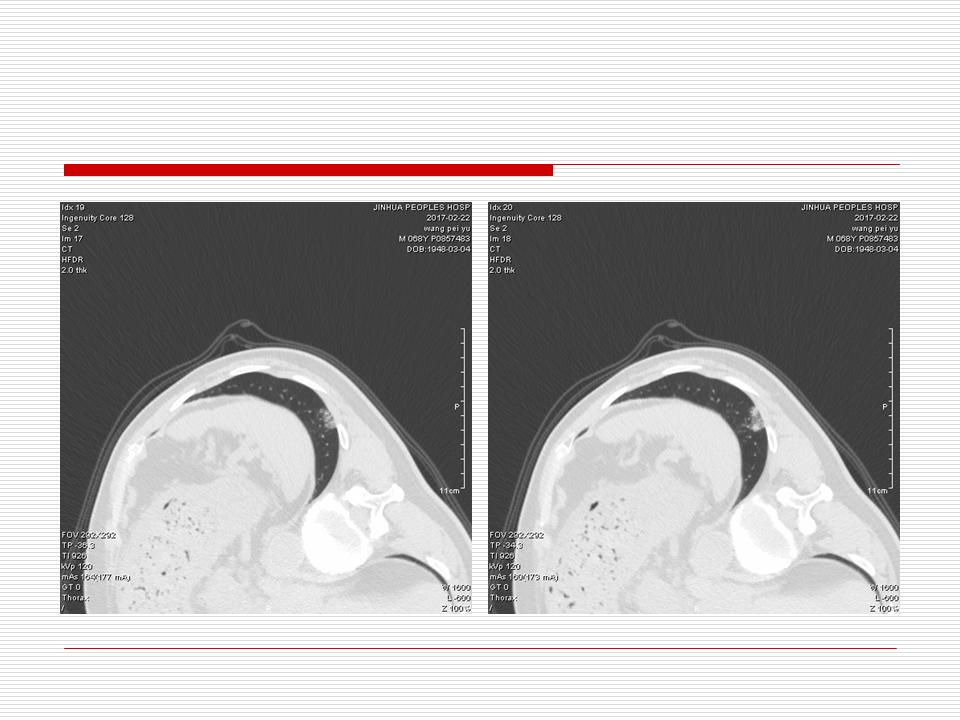

肺部阴影永恒且最重需要鉴别的是:到底是炎症还是肿瘤?但临床的病例中的影像表现难以界定或有些肿瘤特征,同时又有些炎症特点是非常常见的情况。作为临床医生我们怎么去总结分析,并找到之所以是炎症或之所以是肿瘤的细微差别或特点非常重要,也非常有用。2019.12.7浙江省2019年胸心外科学学术年会在宁波召开时,我的临床病例分析与经验总结<那些像肺癌的炎症与像炎症的肺癌>获得在大会交流的机会,以下为该PPT的内容,与你分享,希望对同道有益,有借鉴与启迪。若有探讨与进一不完善的建议,欢迎文末留言讨论: